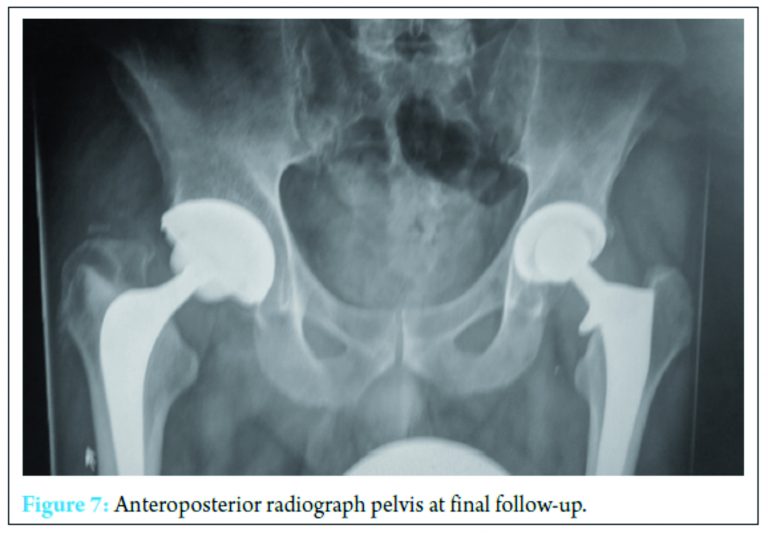

A further washout performed at week three revealed a deep fluid collection so the wound was left open and a vacuum-assisted closure (VAC) device applied. Six separate theater specimens were all negative for microbial growth. Following this, the Microbiology Department advised discontinuing IV piperacillin-tazobactam and IV teicoplanin 400 mg TID and meropenem 1 g TID were commenced. Throughout the first few weeks, alternative sources of infection including endocarditis were excluded and a magnetic resonance imaging revealed no pelvic collection or evidence of osteomyelitis. The VAC drainage remained high and further theater wound inspections identified the deep collection was not recurring. One of the deep tissue samples sent in this period was positive for C. albicans. Although initially thought to be a contaminant, oral fluconazole 400 mg OD was commenced given the poor response to polymicrobial therapy. Despite remaining clinically and biochemically well, the wound failed to progress, and therefore a formal first stage excision arthroplasty was performed 8 weeks following admission, with a Biomet stage one select reinforced cement hip spacer impregnated with gentamicin and vancomycin through an anterolateral approach [7] (Fig. 4). Femoral head histopathology confirmed appearances in keeping with osteomyelitis. Throughout the next 2 weeks, four changes of VAC were required to monitor the wound and ensure no deep collection was persisting, due to a pattern of fluctuating inflammatory markers. Positive C. albicans cultures were obtained from only two out of nine deep tissue samples taken intraoperatively despite the patient being on antimicrobial therapy. Peripheral blood cultures remained negative. A diagnosis of secondary fungal septic arthritis was then made given the recurrent positive C. albicans growth from tissue samples. Oral fluconazole 400 mg OD was escalated to intravenous anidulafungin 50 mg OD and antibiotic therapy discontinued following a 10-week course (Fig. 5). He responded well both clinically and biochemically with a white cell count of 10 × 103 cells/mm3 and CRP of 30 mg/ml. The wound settled slowly and progressively thereafter allowing delayed primary closure 9 weeks following admission. Following wound closure, he remained well with a healing wound and therefore was discharged home on his intravenous antifungal treatment. An uncomplicated second stage procedure was performed 3 months following the first stage procedure with implantation of a cemented total hip replacement. Revision copal cement, impregnated with gentamicin and clindamycin as standard was supplemented with 600 mg grams of anidulafungin antifungal powder [8] (Fig. 6).

The six theater samples were all negative for bacterial and fungal pathogens. The patient recovered well postoperatively with no complications. IV anidulafungin 50 mg OD was continued for a further 3 months through community nursing and then discontinued. Nine months postprocedure, he is currently functioning with pain-free range of motion of the right hip with no complications; however, we must be aware that later recurrence of infection is still a possibility so ongoing follow-up will be required (Fig. 7).